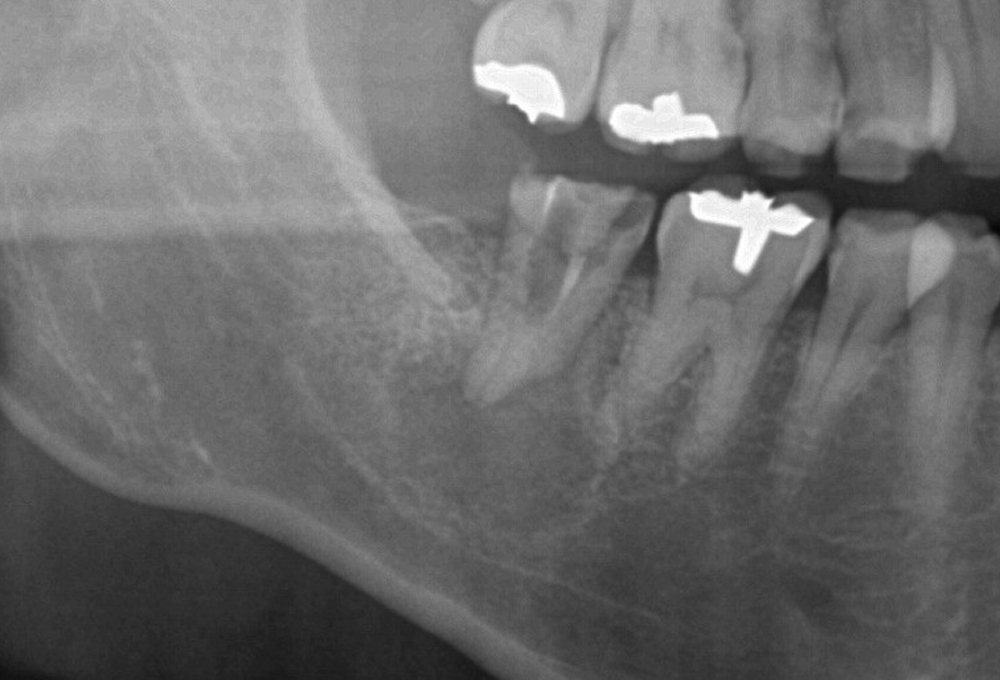

②CTで上顎洞粘膜肥厚 根尖病変確認

③処置後のCT 上顎洞粘膜の肥厚も消失